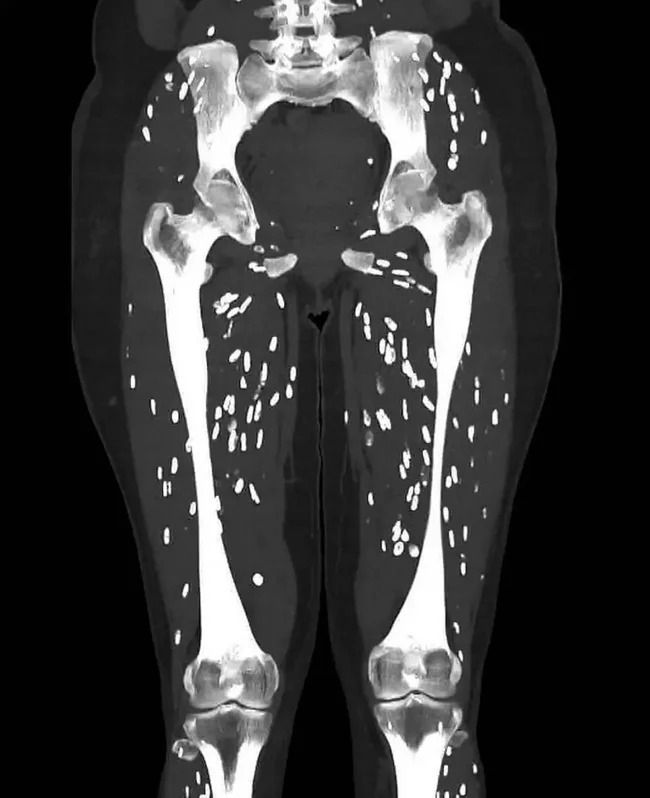

Врач скорой помощи Сэм Гали опубликовал снимок компьютерной томографии, иллюстрирующий последствие употребления полусырой свинины. На изображении мышцы пациентки изрешечены паразитами.

У женщины диагностировали цистицеркоз - инфекция, вызванная личинками паразита Taenia solium, также известного как свиной цепень.

Личинка внедряется в стенку тонкой кишки, попадает в кровеносные сосуды и током крови разносится по организму, формируя кальцинированные кисты в мышцах или мозге. Они могут ощущаться как небольшие комочки под кожей и видны на рентгеновских снимках.